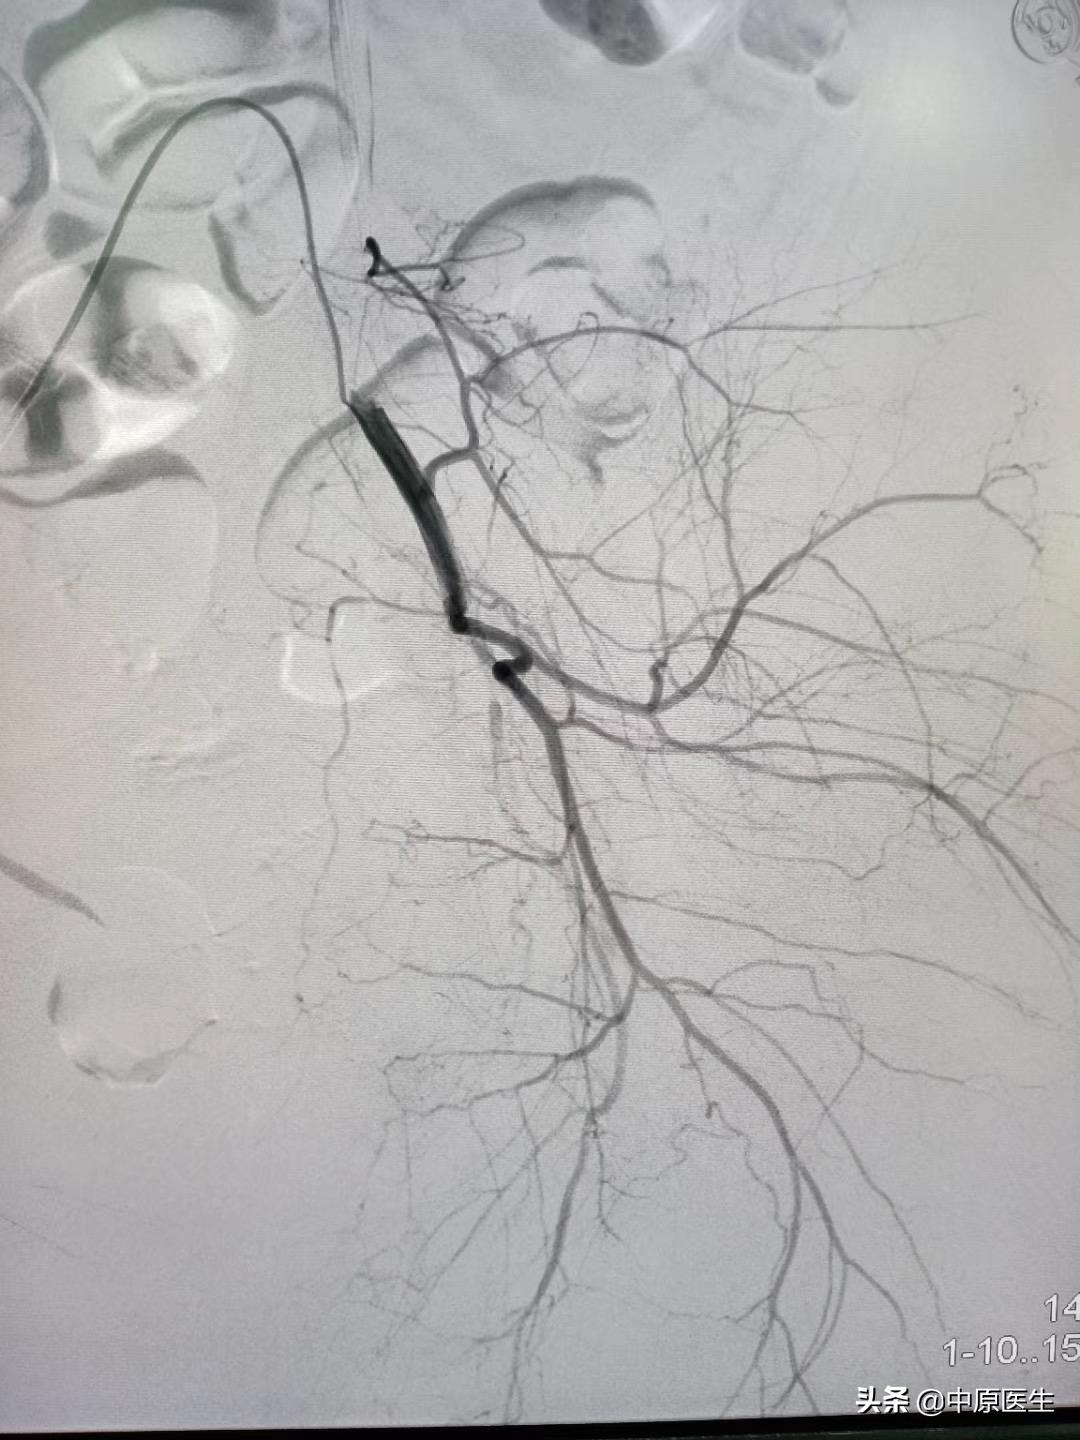

我处理好门诊事宜,十点赶往导管室,按标准预防做好术前防护、术前准备工作。在导管室的护士、技师等积极配合下,手术顺利开展,造影显示左侧子宫动脉近宫颈处有一破口、形成假性动脉瘤,假性动脉瘤破溃,造影剂快速流入宫腔内(相当于找到了河流的决口处);紧急用生物胶栓塞该破口及其远、近端血管(相当于堵住了决口及其上下游,上游流不进来、下游的倒灌不了),复查造影未见造影剂外渗、动脉瘤、静脉早显等异常血管影(成功止血)。然后选择双侧髂内动脉各分支造影未见明显异常血管,再予右侧子宫动脉栓塞。半小时顺利完成手术,病人生命体征平稳。安全送回病房,继续药物治疗。